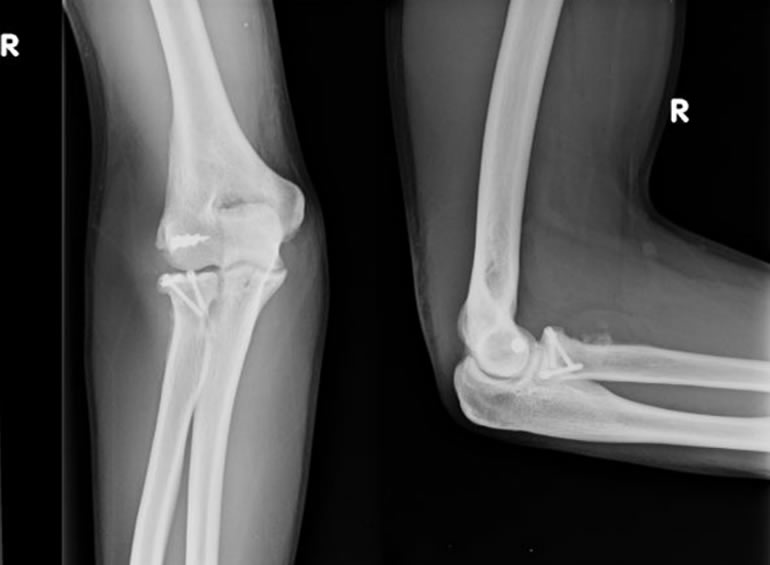

Tras un accidente automovilístico de alto impacto con una serie de secuelas físicas, entre ellas la destrucción de mi codo quede con un brazo sin movimiento. Comencé la búsqueda de opiniones médicas para recuperar mi movilidad perdida y soñando volver a hacer algo tan sencillo como tocar mi cara, en esta búsqueda conocí al Dr Reinares quien me dio una esperanza con la cirugía de Protesis de Codo. Me sometí a dicha cirugía en el año 2016 de la que obtuve maravillosos resultados, recupere mi movilidad tan anhelada que me ha permitido hasta el dia de hoy realizar todas las actividades de mi vida diaria, Tremendamente agradecida de este gran profesional

En mi trayectoria técnico profesional me he visto potenciado de manera acelerada, gracias a las valiosas instituciones en las que estoy colaborando, y de esta manera desarrollar mis habilidades y destrezas quirúrgicas, también mejorando mis debilidades. Con empatía y entusiasmo seguimos mejorando junto a mi equipo de trabajo, la oportunidad de los pacientes a acceder a técnicas quirúrgicas avanzadas y al desarrollo tecnológico, tratando de generar nuevo conocimiento y ciencia en nuestro que hacer.